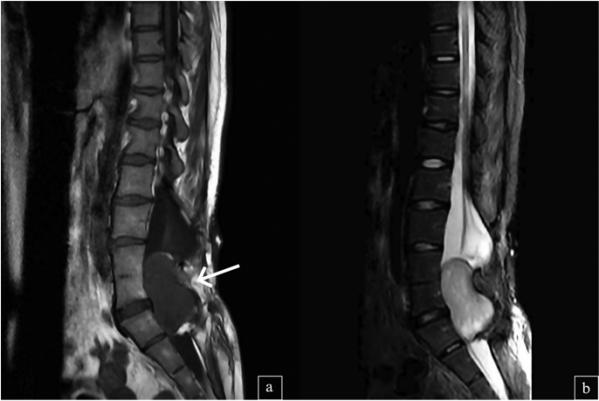

放射学评估,包括脊髓磁共振成像(MRI),在L4-S1水平的椎管内发现一个6×5×3 cm大小的肿块。考虑到患者的脊髓脊膜膨出史,鉴别诊断包括原发性脊髓肿瘤和继发性病变。(图1)随后,患者接受了L4-L5水平的椎板切除术,以手术切除髓内肿瘤,主要目标是缓解脊髓压迫和保留神经功能。术后期间没有任何明显的并发症。

图1、(a1)T1加权腰椎MRI图像显示L4-S1水平椎管内边界清晰的低信号肿块(箭头)。(b)在矢状面T2加权的MRI图像中,6×5×3cm的病灶呈高信号